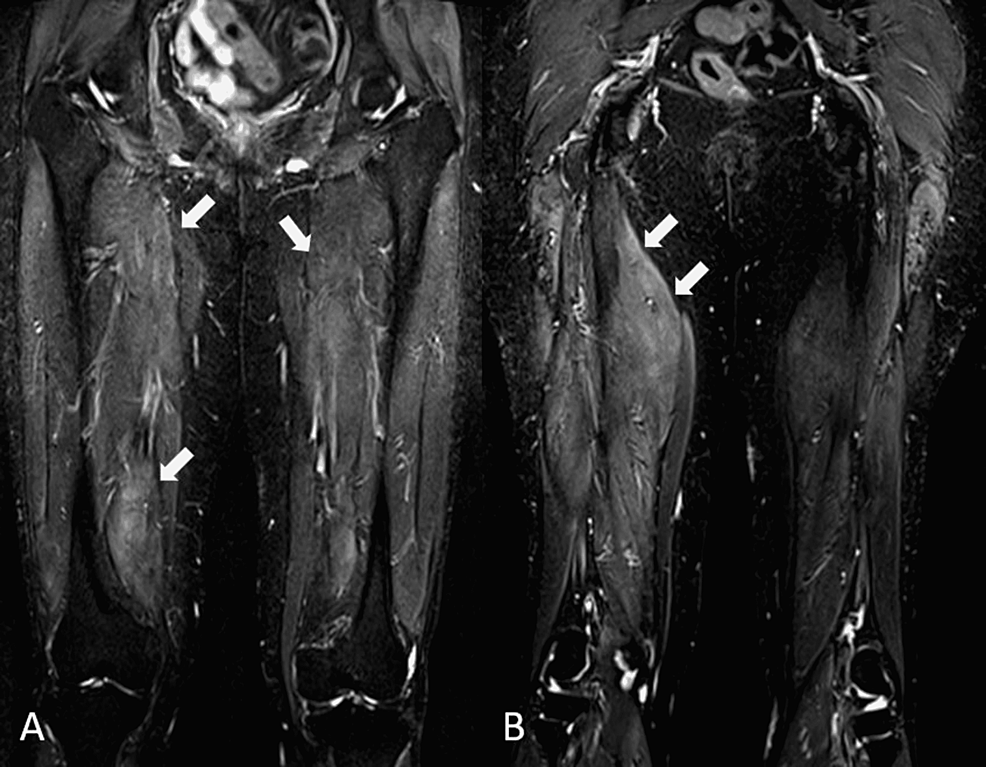

Autoimmune workups (antinuclear antibody, extractable nuclear antibodies, and double-stranded DNA) were negative. Thyroid function profile and erythrocyte sedimentation rate were normal. Serum CK was markedly elevated at 6,981 U/L (NR: <300). She was referred to the rheumatology service for evaluation. Inflammatory myositis was suspected and prednisolone 20 mg daily, vitamin D, and calcium replacement were started. Due to her history of weight loss and mildly elevated carcinoembryonic antigen (5.1 ng/ml, NR: <4.9), upper and lower gastrointestinal endoscopies and CT scans (thorax, abdomen, and pelvis) were done to exclude paraneoplastic manifestations. All were normal. In light of her history of previous statin use, an anti-HMGCR antibody check was done and was found markedly elevated at >200 U/ml (NR: <20), confirming the diagnosis of statin-induced IMNM. An MRI of her thighs showed swollen muscle consistent with myositis (Figures 1A, 1B).

MRI-of-the-thighs

MRI Normal may show muscle edema Diffuse swelling of affected muscle groups. Areas of breakdown with liquefied necrosis Muscle edema